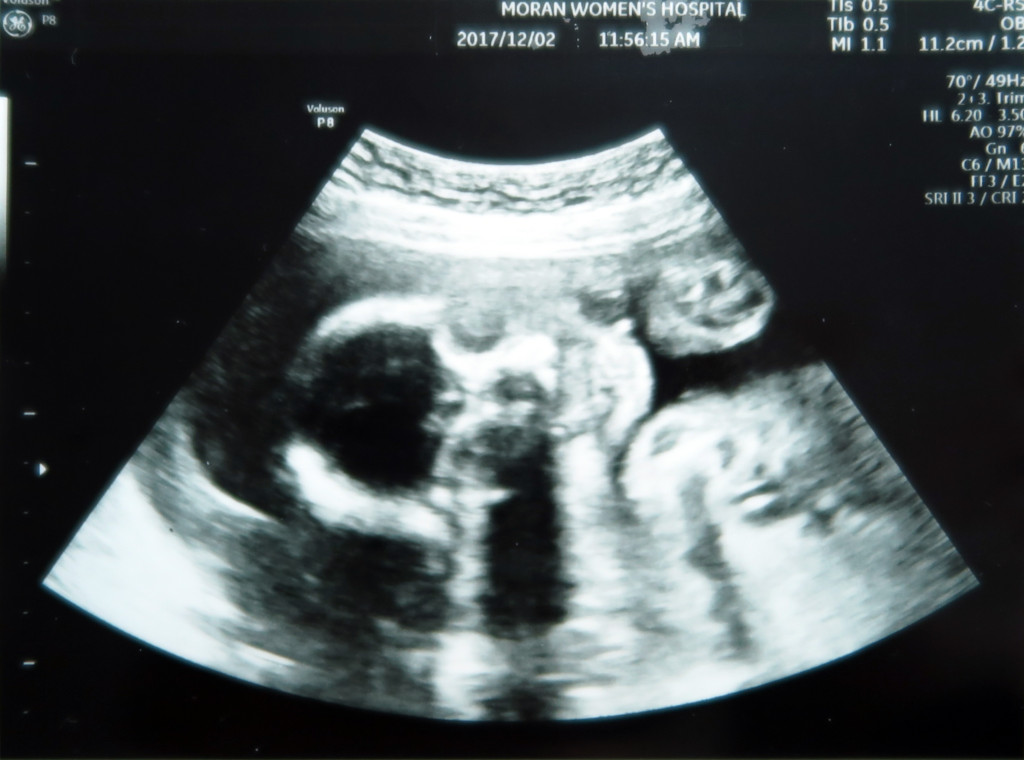

엄마 뱃속에서 콩알만큼 작은 생명이 우리 가족의 일원이 되었다고 신고하네요~

고 작은 녀석의 심장소리는 또 얼마나 우렁찬지.

서현이 때도 들었던 심장소리지만 또 들어도 마음이 울컥합니다.

1차 정밀초음파 때 (13주) 아빠의 매의눈은 봐 버렸습니다 ( ◥◣_◢◤ )

달이 다리 사이에 무언가 있는것을ㅎㅎ

선생님께 재차 무언가 있는 것이냐 물었지만 선생님은 대답이 없으셨어요ㅋㅋ

재차 삼차 묻는 제가 불편하셨는지 선생님의 눈빛은 흔들리고 ㅋㅋㅋ 그 부위 근처만 가면 다른 곳으로 옮기시던 선생님 (◎-◎;)